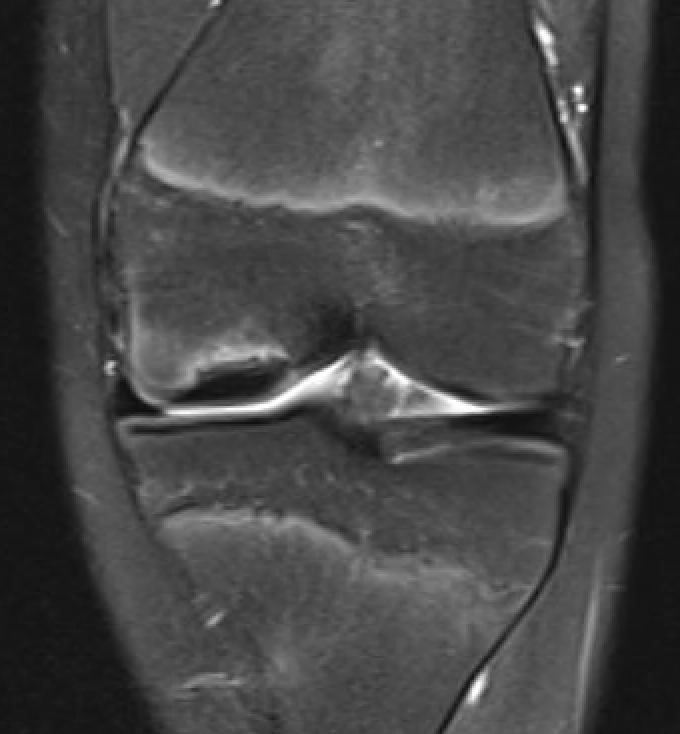

MFC OCD on presentation T2 image 6 months later

Stable lesion with no cysts Stable lesion with cysts